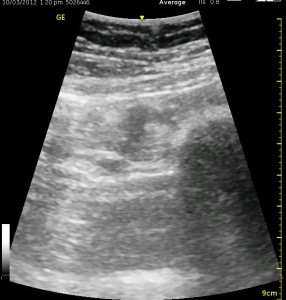

The image above is not an obvious one, and I did that on purpose. You have to get used to the idea that you will not always have a ‘super distinct’ image with this approach, and you will often need to use a number of additional clues to find your target and then to put local around it. I think the only way to really get a handle on being able to identify the basic elements is to look at several images over and over, so I have provided several below for you to use for practice. Note that the sciatic nerve will ‘poke out’ from behind the femur to different degrees depending on your orientation to the femur as well as to how far up or down the femur you go. It will be seen more if you are proximal. See how well you can identify the structures in the images below.